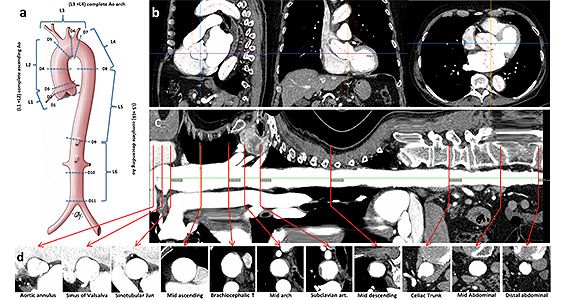

TAIPAN Tübingen Aortic Pathoanatomy Project

Leiter: Dr. med. Krüger

Dissektionen der Hauptschlagader (Aorta) stellen ausgesprochen kritische Notfälle der Herzmedizin dar. Folgen können ein Herzinfarkt, Schlaganfall, und damit Behinderung sein, in einzelnen Fällen führen Aortendissektionen trotz sofortig durchgeführter Notoperationen zum Tode. Die Erkrankung entsteht plötzlich und unvorhersehbar, eine wirkungsvolle Prophylaxe und Erkennung von Risikopatienten ist zum heutigen Tage nicht möglich. In einem groß angelegten Forschungsprojekt analysierten wir Computertomographien unserer Patienten der letzten 10 Jahre um Merkmale zu finden welche die Vorhersage einer Aortendissektion ermöglichen. Hierbei konnten wir die Längenparameter der aufsteigenden Aorta und des Aortenbogens als Prädiktoren für Aortendissektionen identifizieren. Wir entwickelten einen Algorithmus zur Risikovorhersage von Aortendissektionen.

Wir können zwischenzeitlich all jenen Patienten die wir in unserer Aortensprechstude [LINK] versorgen eine Diagnostik entsprechend dem genannten Algorithmus anbieten. Wir arbeiten auch weiter an der Verbesserung der Diagnostik, der Früherkennung und Prophylaxe gefährlicher Aortenerkrankungen.